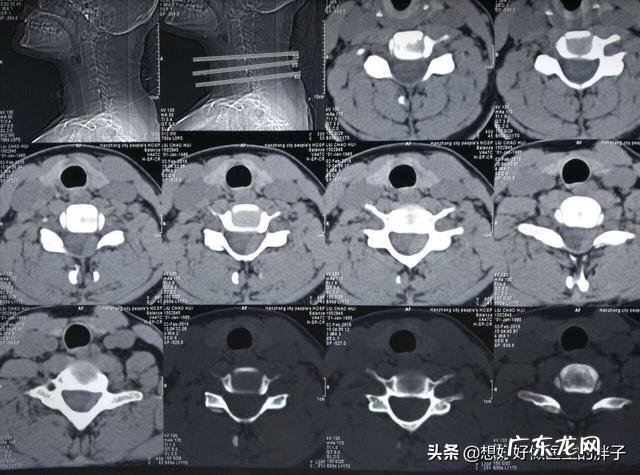

因为这种情况应该给予进行查体,比如我们患者坐正,手放在患者的头部顶上,自上而下向下施加一定的压力,如果能诱发患者症状的加重或者是诱发出患者的症状,那么很可能存在着颈椎的间盘突出 。此时应该给予患者进行颈椎的核磁检查或者CT检查,明确是否存在颈椎间盘突出或者是更严重的脱出或者是游离状态 。